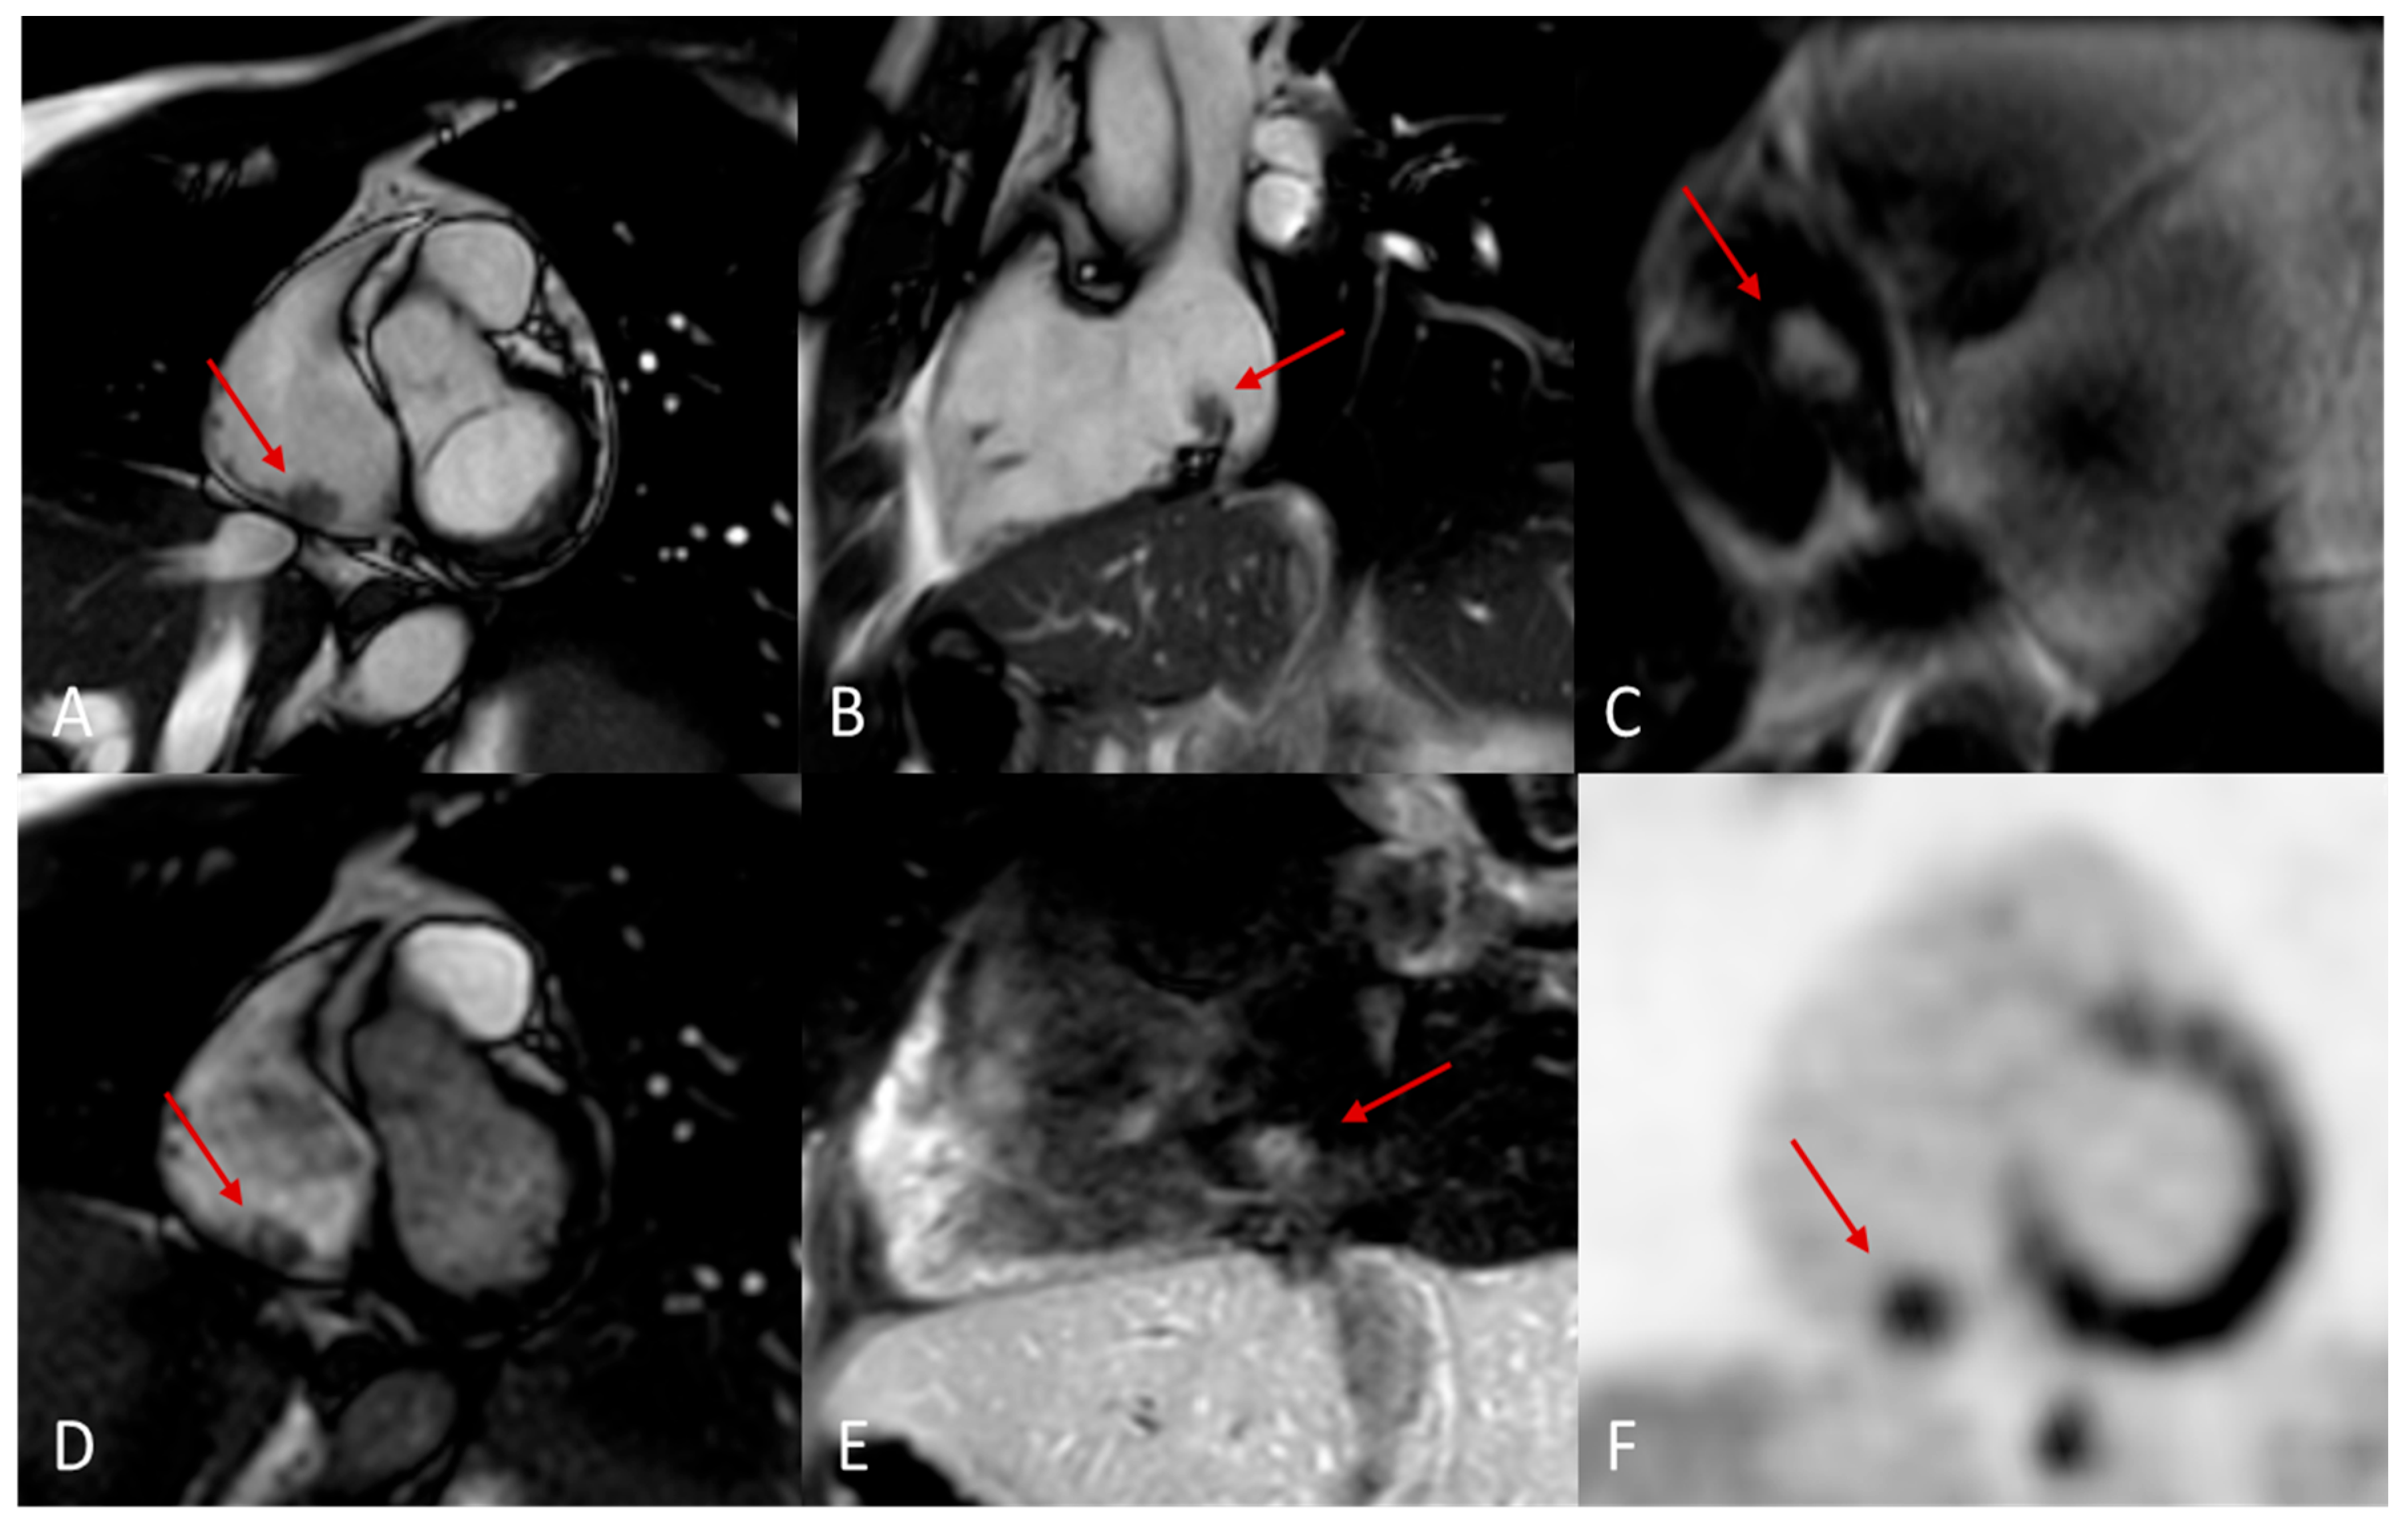

Figure 11. Giant hemangioma originating from the anterior-basal interventricular septum, as seen on CT (A), showing progressive and intense enhancement on delayed post-contrast CT acquisition (B). The lesion demonstrates heterogeneous hypointensity on T2-steady state-weighted MRI (C), marked hyperintensity on fat-saturated T2-weighted images (D).

Figure 12. Massive sarcoma of anterior-lateral wall of left ventricle with massive pericardial effusion and left pulmonary lobe metastases. Isodense in T2-weighted images (A) and T1 (B) with inhomogeneous LGE (C).

5.7. Hemangioma

Cardiac hemangiomas are rare vascular malformations made up of clusters of endothelial-lined channels separated by thin fibrous and fatty septa. Typically asymptomatic, they can nonetheless cause pericardial effusion, innocuous murmurs, arrhythmias, tamponade, cardiac arrest or even sudden death. Histologically they fall into capillary, cavernous or arteriovenous types and may involve any layer of the heart muscle, most commonly the left atrium. On echocardiography they appear as hyperechogenic masses; CT at baseline shows heterogeneous density that becomes markedly hyperenhanced after intravenous contrast; and MRI reveals a heterogeneous lesion that is iso- to hyperintense on T1-weighted sequences, intensely hyperintense on T2-weighted images, with equally heterogeneous contrast uptake [22,46,47].